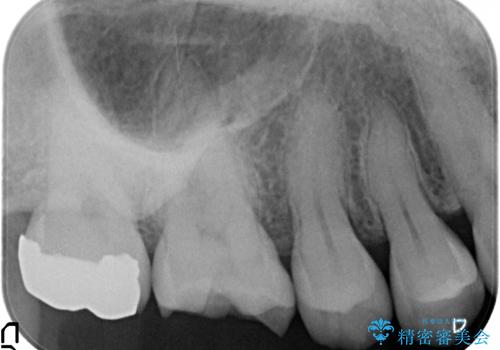

保険適応の銀歯を除去し虫歯を取ったのち、ジルコニアクラウンで置き換えていきます。

- 55万円(仮歯・ジルコニアクラウン×5)費用は治療当時の料金となります